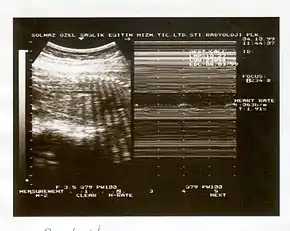

A biophysical profile (BPP) is a prenatal ultrasound evaluation of fetal well-being involving a scoring system,[1] with the score being termed Manning's score.[2] It is often done when a non-stress test (NST) is non reactive, or for other obstetrical indications.

The BPP has five components: four ultrasound (US) assessments and an NST. The NST evaluates fetal heart rate and response to fetal movement. The five discrete biophysical variables: